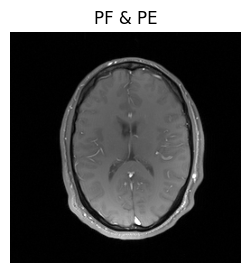

show_images(magnitude_fully_sampled, magnitude_pe_pf, titles=['fully sampled', 'PF & PE'])

Well, we got an image, but when we compare it to the previous result, it seems like the head has shrunk. Since that’s extremely unlikely, there’s probably a mistake in our reconstruction.

../_images/d78db753b60ca62406efa3a2dd0649b7e39cecc9aef00870b725203c472c3750.png

Voila! We’ve got the same brains, and they’re the same size!